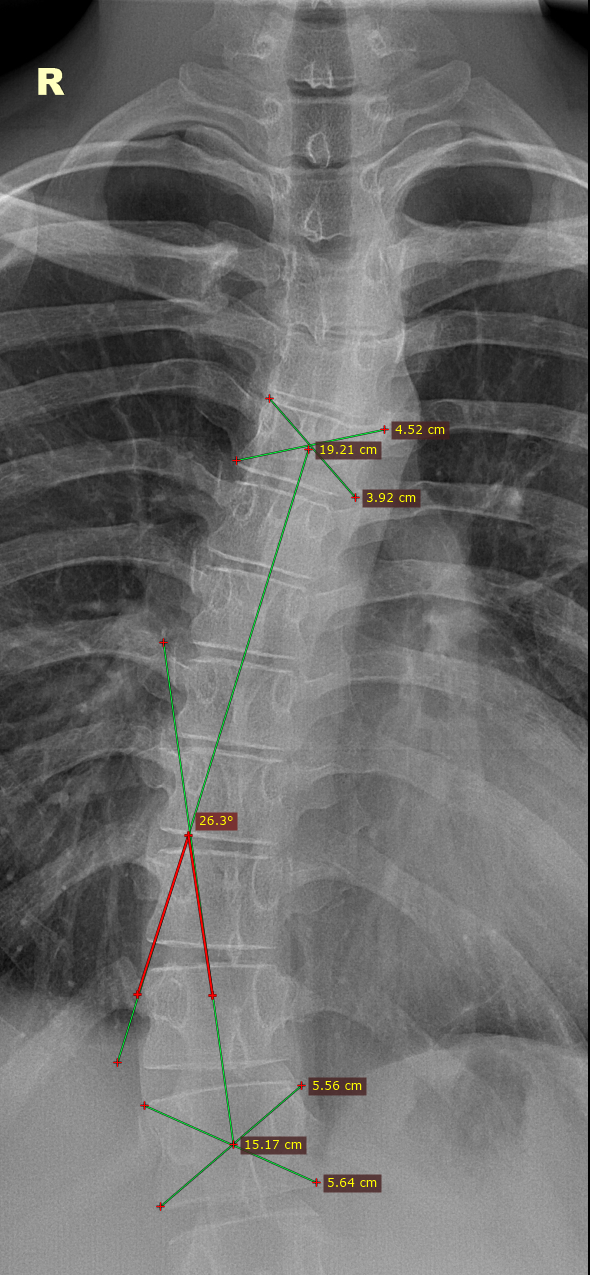

При укорочении нижней конечности,X и O-образных деформациях нижних конечностей, нужно направлять призывников на панорамную рентгенографию нижних конечностей(это современный метод, который позволяет получить единое рентгеновское изображение всей длины обеих ног, от костей таза до стоп. Для этого используются современные аппараты, которые автоматически «сшивают» серию снимков в одно цельное изображение), но такая аппаратная возможность есть не во всех мед. учреждениях.

Также, для подтверждения укорочения нижней конечности используется тест для определения истинной длины нижней конечности. Чтобы точно измерить длину нижней конечности, необходимо, чтобы пациент лежал на плоской твердой поверхности. Обе ноги должны находиться в одинаковом положении. Измерение производится от передней верхней ости подвздошной кости до дистальной медиальной лодыжки на той же стороне. Затем сравниваются данные, полученные с обеих сторон.

У выше представленного призывника, при измерении истинной длины нижних конечностей, выявлено укорочение правой нижней конечности на 2.5 см., что соответствует ст.69в-В(ограниченно годен к в/сл)